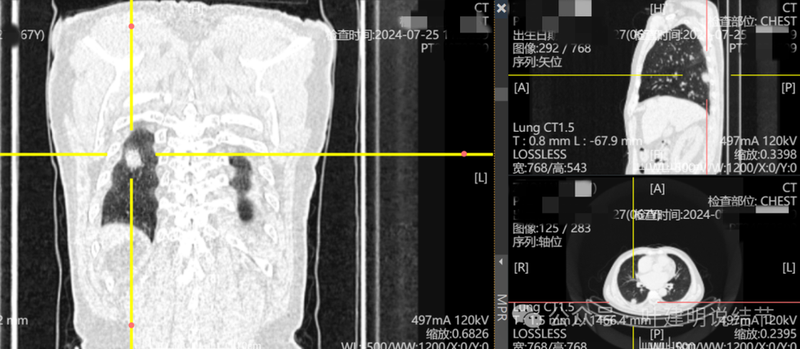

这是冠状位、矢状位与轴位的影像。